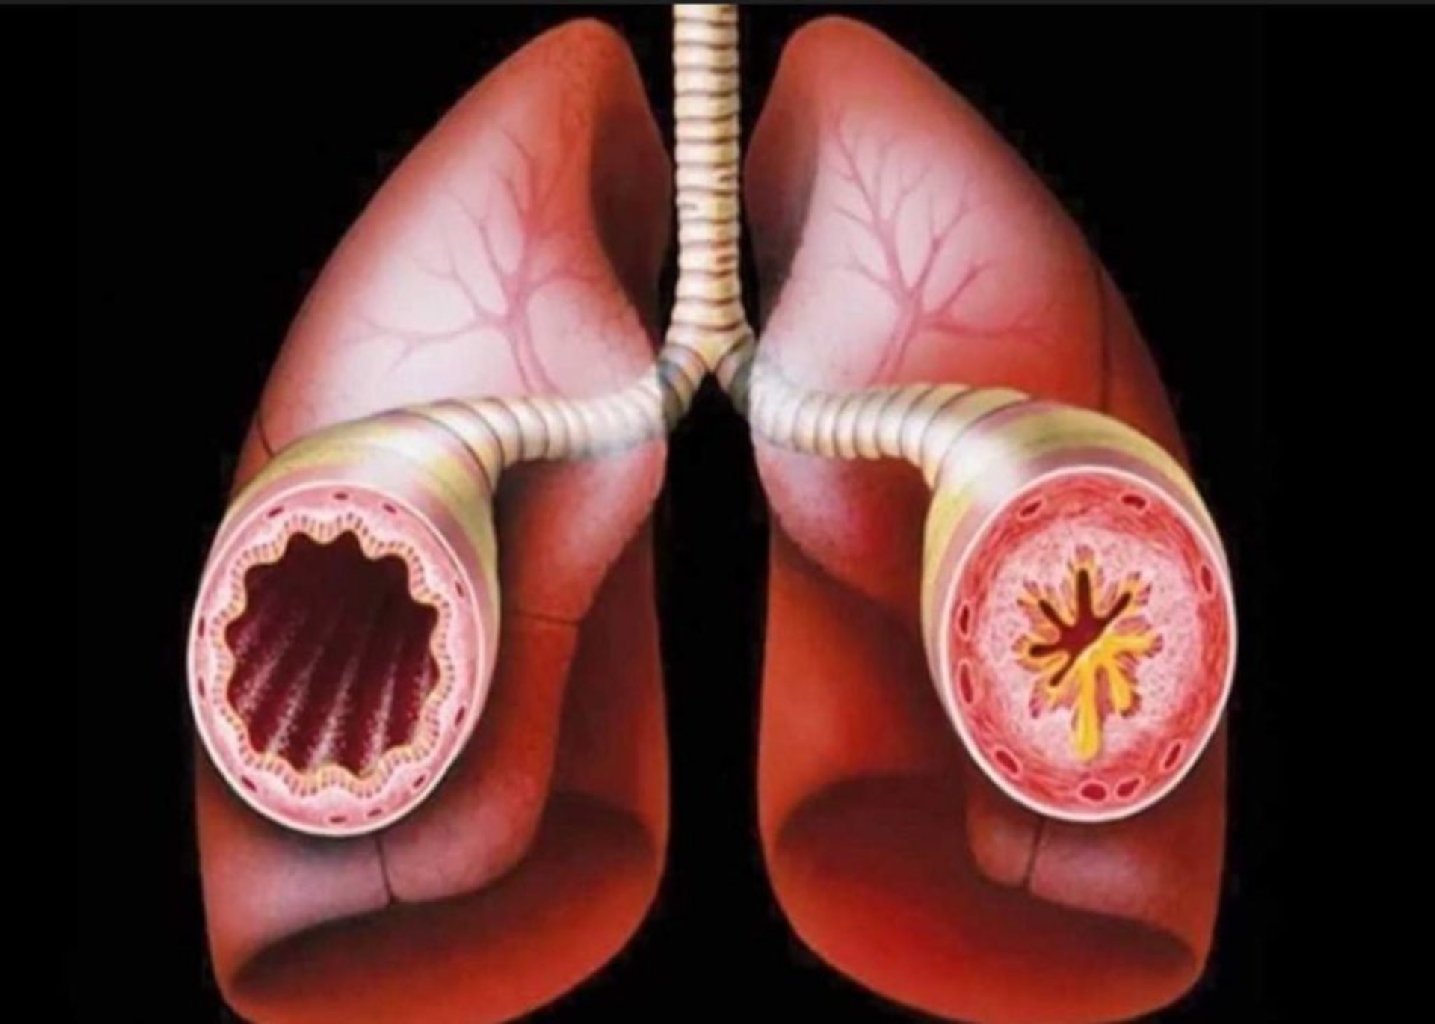

Bronxial Astma: Səbəblər: Bronxial astma genelliklə alərjenlər, küləklər, soyuq hava, və ya fi ...

Bronxitin Səbəbləri və Növləri Akut Bronxit: Üstün yol infeksiyalarının, xüsusilə virusların n ...

Kəskin Bronxitin Səbəbləri Viruslar: Ən yaygın səbəb üst tənəffüs yolu infeksiyalarına səbəb o ...